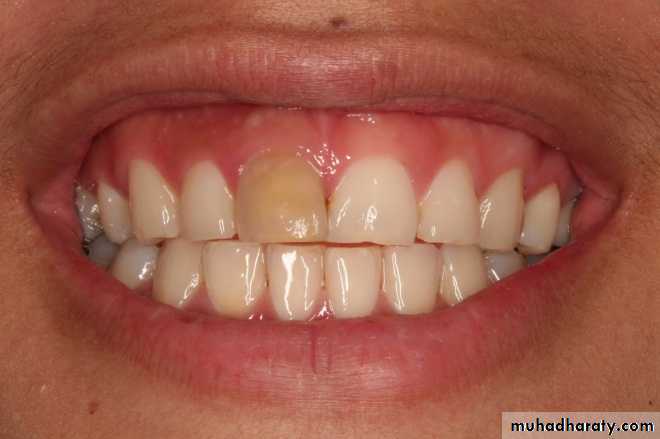

• “Pink Tooth” is the pathognomic feature of internal root resorption (especially in the crown).

• Clinically:“Pink Tooth” appearance

• When external root resorption extends to crown, it gives “Pink tooth” appearance